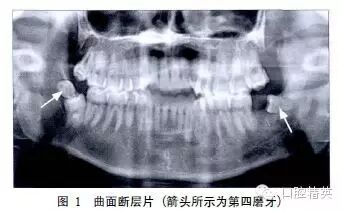

临床检查:48未萌,47远中牙龈肿胀,探及盲袋;38拔牙窝存在,创口新鲜。口腔全景片(图1)显示:双侧下颌均存在第四磨牙。48垂直阻生,49水平阻生于48冠方;38拔牙窝存在,39水平阻生。